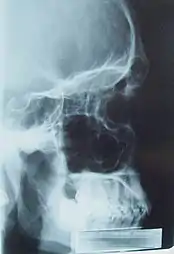

Важным направлением является медицинская физика, и её подобласти: ядерная медицина, радиотерапия и медицинская визуализация.[2] От рентгена до МРТ и ПЭТ: медицинская физика обеспечивает большую часть диагностических возможностей современной медицины наряду с предоставлением многих вариантов лечения.

Рентгеновский снимок мужского черепа